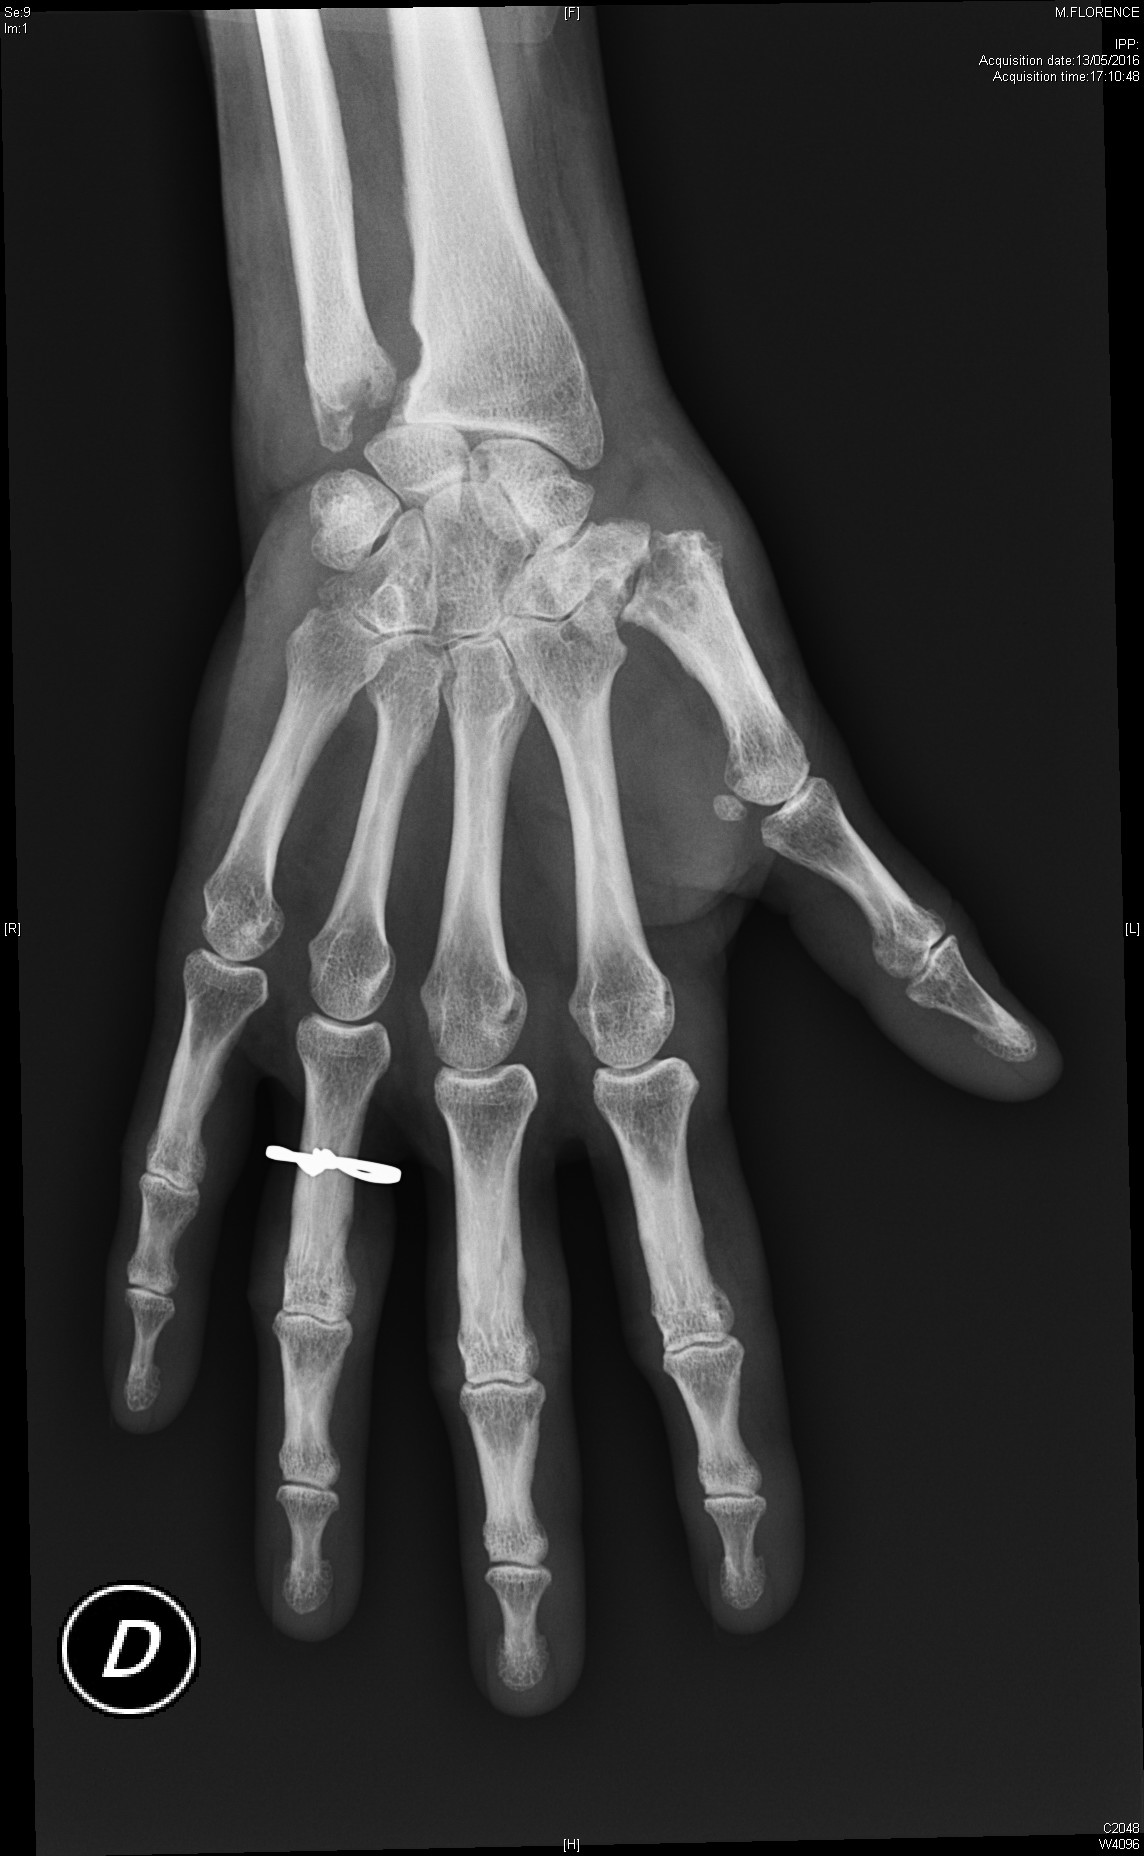

Calcinose dans le cadre d'une sclérodermie systémique